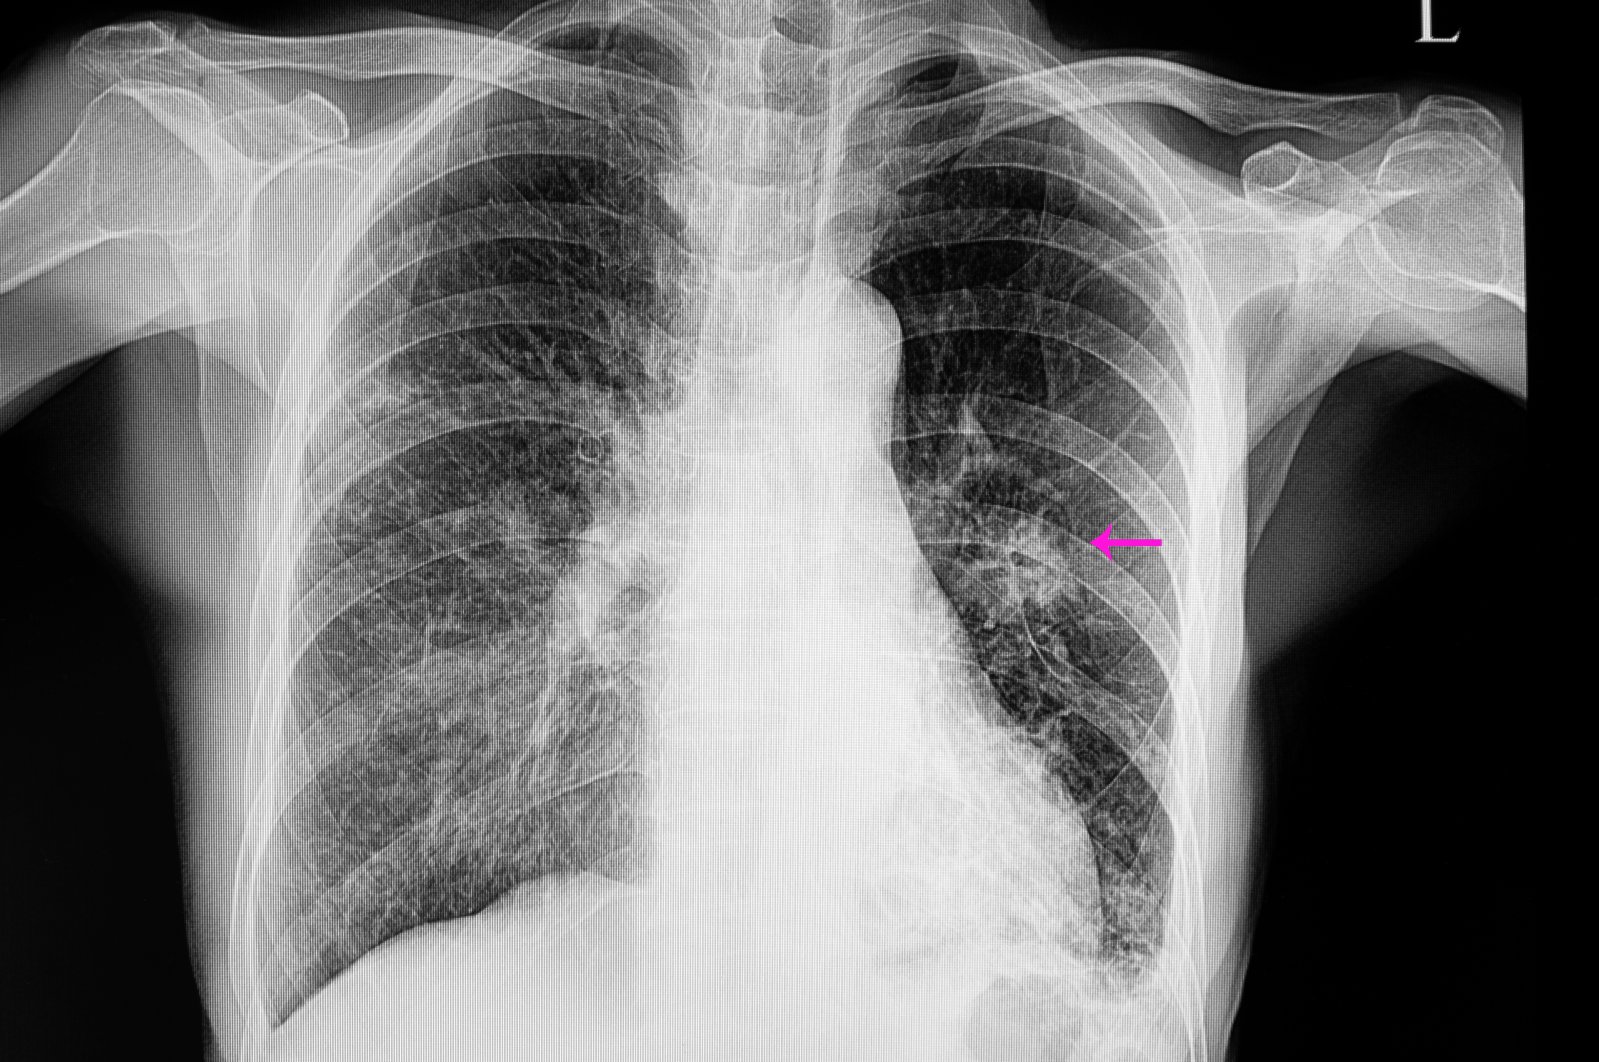

Some of the common symptoms for pneumonia include cough, shortness of breath, chest pain, and general fatigue. To diagnose pneumonia, a doctor will use a stethoscope to check a patient's breathing, listening for a characteristic crackling sound, similar to the sound of crumpling paper, says Tianshi David Wu, a pulmonologist at Baylor College of Medicine. "That's all that's needed to diagnose pneumonia," Wu says, adding that if a doctor is still unsure, they can also order an X-ray of the lungs, which will confirm the diagnosis.